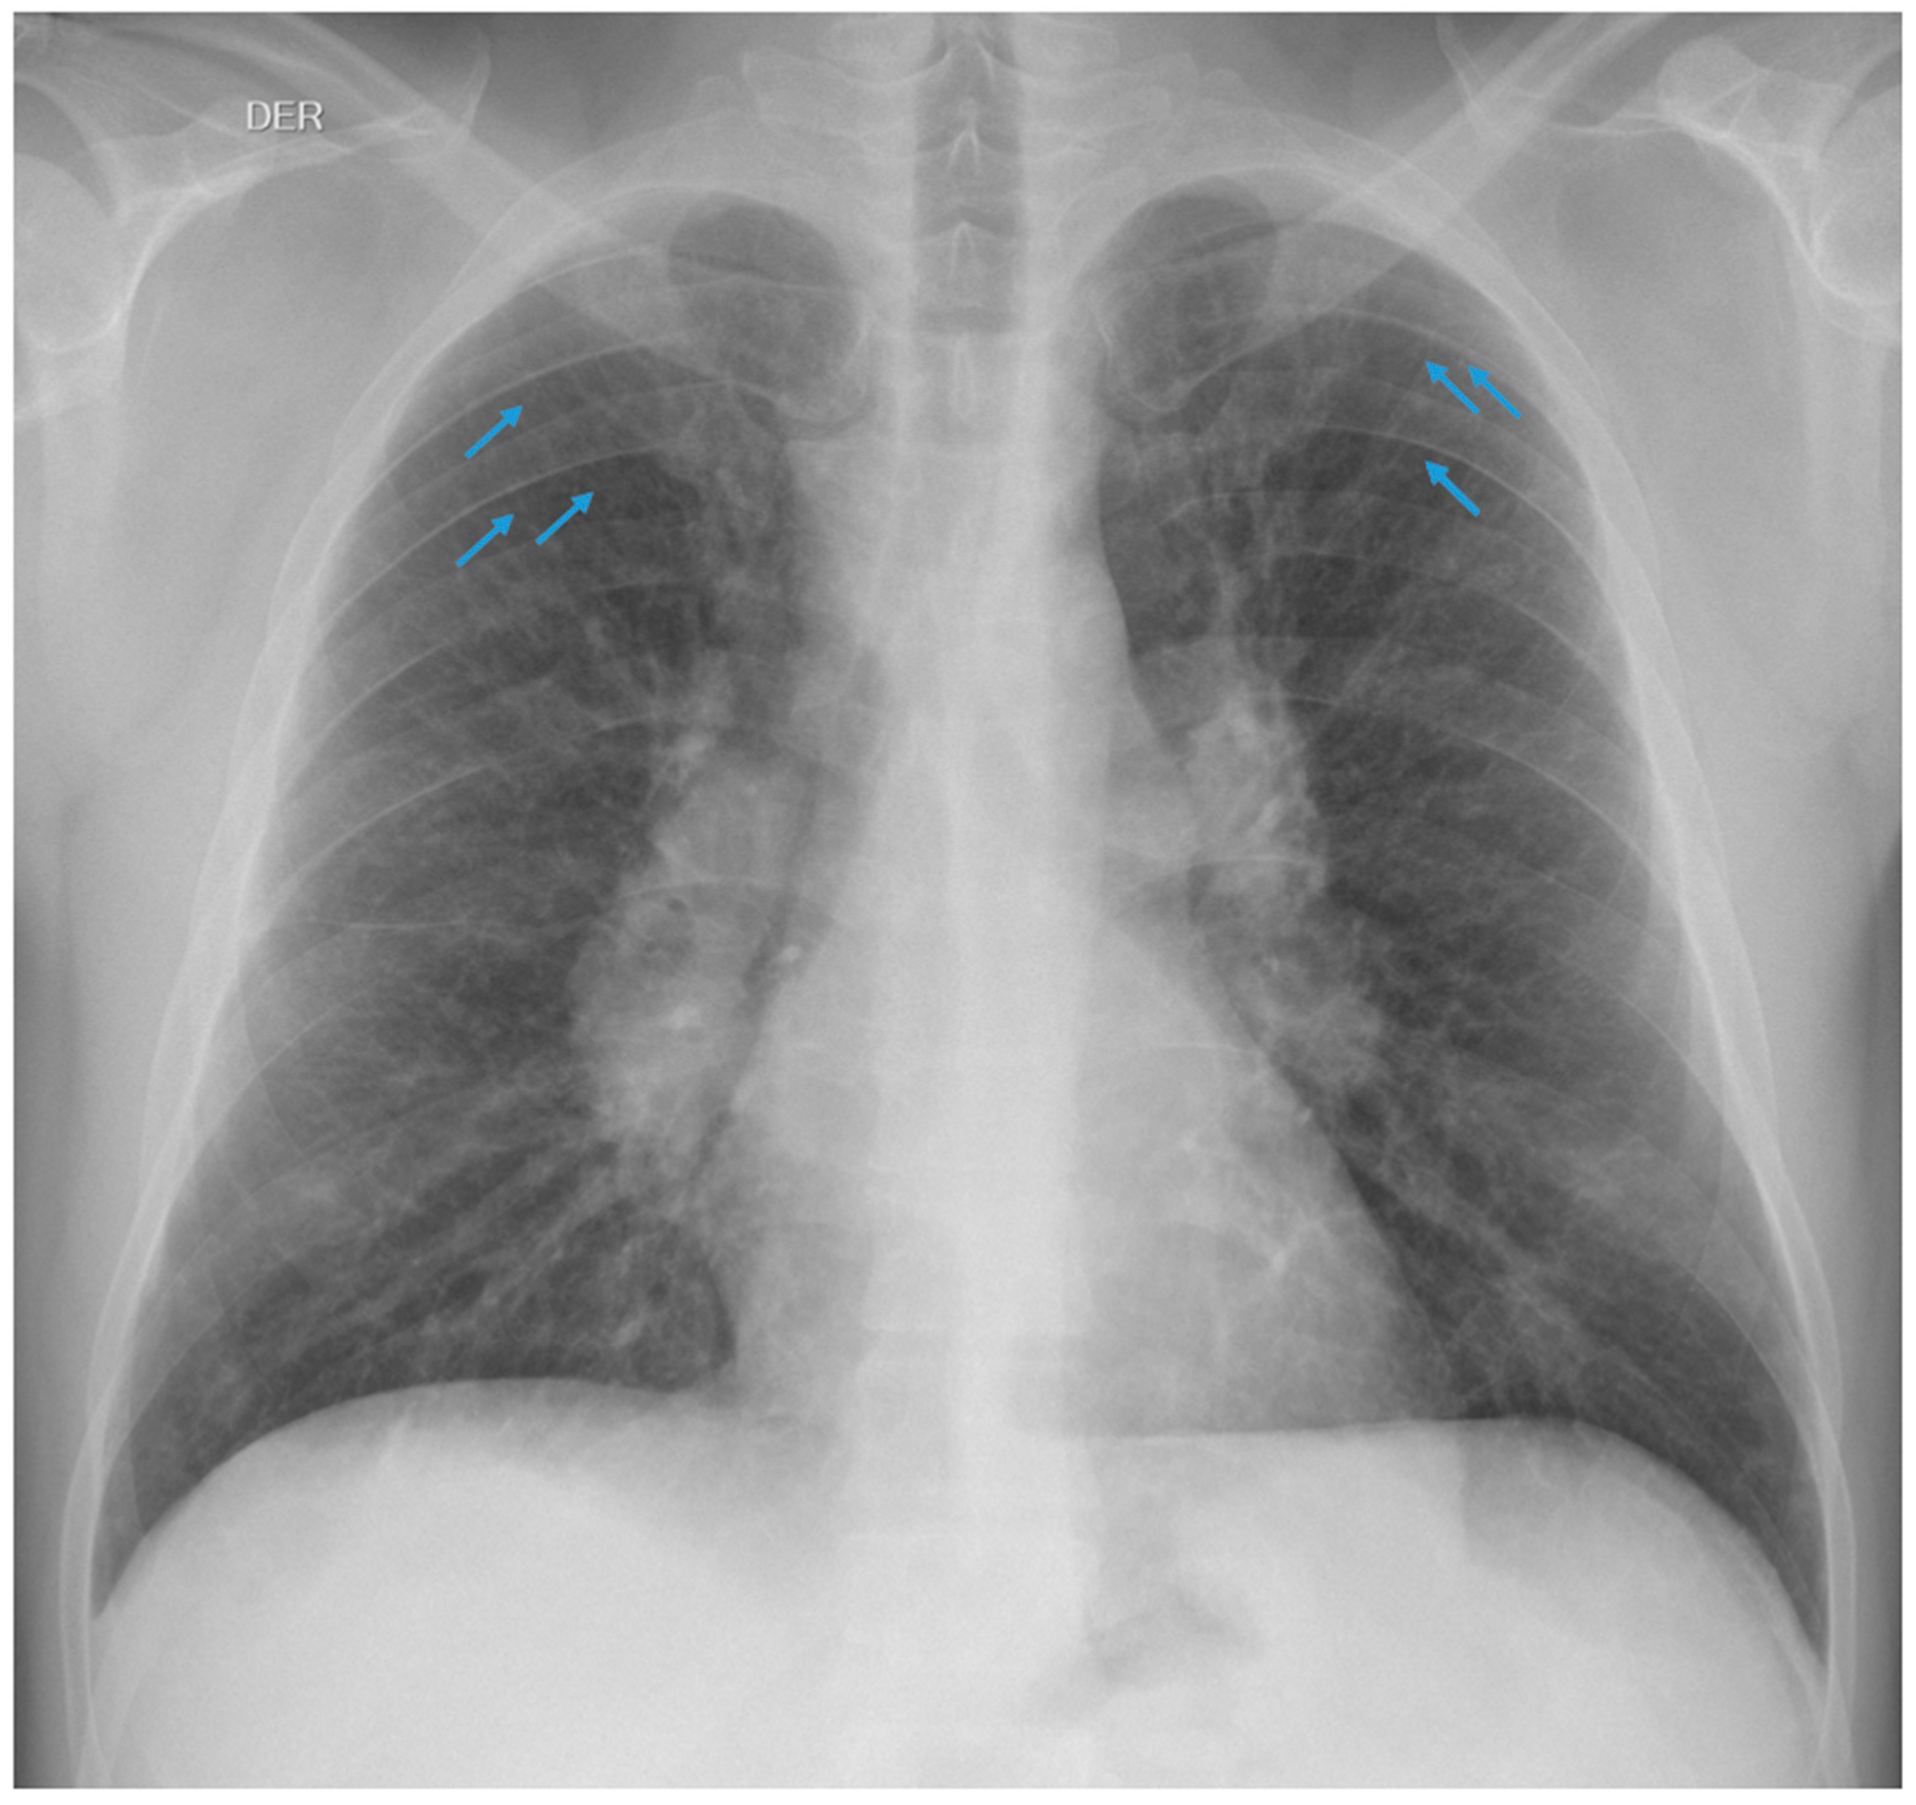

3.1.1. Case 1